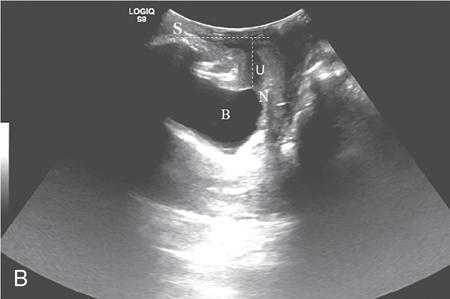

PELVIC FLOOR IMAGING – ANTERIOR AND MIDDLE COMPARTMENTS Anu Epean, Deepa Korula The term ‘Pelvic floor disorder’ refers to dysfunction of the pelvic floor musculature and connective tissues which provide support for the pelvic organs. This can produce a wide range of symptoms such a urinary incontinence, straining to void, dyspareunia, constipation, faecal incontinence and organ prolapse. The greatest risk factors for pelvic floor disorders are female sex and advanced age. Other risk factors include obesity, pregnancy, multiparity, smoking, connective tissue disorders. The pelvic floor is broadly divided into three compartments. The bladder and urethra form the anterior compartment. The vagina and uterus form the middle compartment and the posterior compartment comprises of the rectum and anal canal (Fig. 7.16.1.1). The attachment of the fascia, muscles and the ligaments to the bony pelvis form the support for these structures. From cranial to caudal, there are three layers which make up the pelvic floor – the endopelvic fascia, the pelvic diaphragm and urogenital diaphragm. This is the most cranial layer of pelvic floor, lying deep to peritoneum. It is a fine structure, comprising of a network of connective tissue which encases the pelvic viscera, provides support to the pelvic organs and maintains their anatomic relationship. There are several condensations of this fascia and ligaments which provide support in each of the pelvic compartments. In the anterior compartment, a fascial condensation called pubocervical fascia extends from anterior vaginal wall to the pubis. Tear in the pubocervical fascia can cause cystocele and urinary incontinence. There are three groups of ligaments which provide urethral support – periurethral, paraurethral and pubourethral ligaments. The periurethral ligaments arise from medial fibres of pubococcygeus and pass ventral to urethra. The paraurethral ligaments connect the lateral wall of urethra to periurethral ligament and pubourethral ligament connects the lateral wall of urethra to arcus tendineus. The urethra lies on a Hammock-like supportive layer of endopelvic fascia and anterior vaginal wall, which are stabilized by attachment laterally to arcus tendineus and levator ani (Fig. 7.16.1.2). In the middle compartment, condensations of the endopelvic fascia which attach the uterus to the lateral pelvic wall is called parametrium, which is made up of the uterosacral and cardinal ligaments. The uterosacral cardinal ligament complex supports and suspends the cervix and upper vagina above the levator plate. More inferiorly, the paracolpium attaches the vagina to the lateral pelvic wall. There are three levels of fascial support to the vagina: In the posterior compartment, the perineal body located within the rectovaginal septum supports ligaments and muscles and prevents abnormal widening of levator hiatus (Fig. 7.16.1.3). The rectovaginal fascia extends from posterior wall of vagina to anterior rectal wall. A tear in the rectovaginal fascia is the cause for an anterior rectocele. Arcus tendineus levator ani (ATLA) is formed by the condensation of the endopelvic fascia laterally, along the pelvic sidewall. This extends obliquely from inferior pubic symphysis to ischial spine and provides lateral support to the pelvic organs and attachment of the levator ani. Fascial condensations are not visualized on imaging; however, organ prolapse, due to deficiency in any of these, can be detected on MRI. The levator ani and the coccygeus muscles make up the pelvic diaphragm. The levator ani is the primary muscle of the pelvic diaphragm and is attached to the pubis and to the ATLA laterally on both sides. The slow twitch fibres of the levator ani continuously contract, maintaining tone to the pelvic floor and suspending the pelvic organs in the correct position. The two most important components of the levator ani are the iliococcygeus and puborectalis muscles. The iliococcygeus arises from external anal sphincter and has a curved shape, concave inferiorly. It fans out laterally to its insertion in the posterior part of arcus tendineus (Fig. 7.16.1.4A and B). Posteriorly, in the midline, condensations of ilococcygeus form a firm raphe anterior to coccyx called the anococcygeal ligament or levator plate. The pubococcygeus muscle is a component of the levator ani. It forms the anteromedial part and is a thick bundle of fibres arising from the pubis and anterior portion of arcus tendineus. It extends horizontally back to behind the rectum, medially forming the margin of urogenital hiatus (Fig. 7.16.1.5A). The anorectal and urogenital hiatus are closed by the contraction of the pubococcygeus muscle. This enables support during rest and in situations where the intraabdominal pressure is increased. The medial fibres of pubococcygeus, depending on their attachment to urethra, vagina, anus and rectum are termed as pubourethralis, pubovaginalis, puboanalis and puborectalis, collectively as pubovisceralis. The puborectalis forms a sling around the rectum (Fig. 7.16.1.5B). The muscles of the pelvic diaphragm are well delineated on MRI. The urogenital diaphragm or perineal membrane is the most caudal layer of the pelvic floor. It has a triangular appearance, extending from the pubic symphysis and the ischiopubic ramus to the posterior perineal body. It is ventral to the external anal sphincter and perineal body. It is attached to the surrounding structures such as the perineal body, external anal sphincter, vagina and the bulbocavernosus muscle. Imaging has an increasing role in the evaluation of pelvic floor disorders. Clinical examination alone has a low sensitivity and specificity for the detection of multicompartment involvement and organ prolapse. Imaging helps to detect involvement of multiple pelvic compartments and thus to plan surgery. Ultrasound, MRI and conventional imaging which includes voiding cystourethrography, evacuation proctography and dynamic cystocolpoproctography (DCP) are used to evaluate the pelvic floor. It is easily available, cheap and does not involve ionizing radiation. In the evaluation of the anterior compartment, ultrasound is more reliable than MRI. Transperineal ultrasound using 2D, 3D or 4D techniques along with dynamic imaging helps to evaluate pelvic floor dysfunction. Patient is placed in a dorsal lithotomy position for a transperineal scan although a standing position can also be used. Convex transducer (2–6 MHz) or endoluminal transducers (endovaginal/endorectal) maybe used. In a midsagittal translabial scan, the anatomic relationship of urethra, bladder, vagina, cervix and anorectum can be studied and the relative position of these organs determined by use of certain measurements. The bladder-symphysis distance (BND) is the distance between the bladder neck and lowest margin of symphysis pubis and demarcates position of the bladder neck. Measurement of BND is made at rest and during Valsalva manoeuvre and the difference in BND between the two, gives the measure of bladder neck descent. There are no definite values to indicate normal descent but there is a proposed cut off of 20, 25, 30 mm to indicate hypermobility (Fig. 7.16.1.6A and B). The proximal urethra rotates posteroinferiorly during Valsalva manoeuvre and this can be measured by the posterior urethrovesical angle (β) or the gamma angle. The posterior urethrovesical or retrovesical angle (β) is the angle between a line through the urethral axis and the line through the trigonal surface of the bladder and varies from 90–120 degrees normally. This may increase to 160–180 degrees and can be associated with funnelling of bladder neck. The gamma angle is the angle between a line through the inferior margin of pubic symphysis and the urethrovesical junction. This is seen on Valsalva manoeuvre or at rest in patients with stress incontinence (Fig. 7.16.1.7). Color Doppler can demonstrate urine leakage on performance of Valsalva or at rest. Other abnormalities that can be detected on transperineal ultrasound are cystocele, urethral diverticulum, Gartner duct cyst, foreign body or bladder tumour. 3D pelvic ultrasound is useful to evaluate pelvic floor dysfunction and to study the urethra, levator ani complex, paravaginal supports, prolapse and implant imaging. 4D ultrasound helps in real-time, dynamic imaging of pelvic floor. In the middle compartment, although uterine prolapse is often clinically evident, it can also be detected by ultrasound. Uterine prolapse can be also quantified by measuring maximum descent of uterus from the reference point which is the inferior margin of pubic symphysis. Ultrasound is also useful to evaluate for surgical planning in a large retroverted uterus with an anteriorly placed cervix causing voiding symptoms. MRI is useful in the evaluation of pelvic floor as it provides good anatomic detail about the pelvic floor muscles, ligaments because of its inherent superior soft tissue resolution. In addition, dynamic MRI yields functional information. MRI defecography is a dynamic study performed to study the posterior pelvic compartment but it also gives information about the anterior and middle compartments. It can be performed both with closed magnet and open magnet systems. The patient is positioned supine with phased array coil around pelvis in a closed magnet system. In an open magnet system, the patient is in a sitting and more physiological position; however, due to the lower signal to noise ratio and lower resolution, a closed magnet system is preferred. Bowel preparation with use of laxative on night before the scan is optional. Voiding prior to the study is encouraged since an overdistended bladder can cause misinterpretation of results. Presence of some urine in the bladder is however, helpful to detect anterior vaginal prolapse. Instructions are given to the patient, prior to the procedure, about the ‘rest’, ‘squeeze’, ‘strain’ and ‘defecate’ phases of dynamic imaging, to ensure that movement or lifting of the pelvis does not occur during these manoeuvres. The rectum is filled with up to 200 mL of ultrasound gel. The patient is made to wear an adult diaper and covered with an incontinence pad on the gantry. Vaginal gel, ∼50 mL maybe introduced since this helps to delineate anatomic landmarks and detect uterovaginal prolapse. Initial large FOV T1 localizer scans help to identify the midline sagittal section of pelvis. T2-weighted fast spin echo, high-resolution sequences in sagittal, axial, coronal planes are used to obtain anatomic detail. This is followed by dynamic imaging of the pelvic floor with use of steady state imaging sequences such as True fast imaging with steady state precession (TrueFISP Siemens) and balanced fast field echo (balanced FFE Philips). Steady state sequences have the advantage of short acquisition times and higher signal to noise ratio and hence useful to obtain rapid serial midsagittal images while patient performs ‘squeeze’, ‘strain’ and ‘defecates’. There are several points and lines for measuring and staging pelvic organ prolapse on MRI; however, the PCL line is said to have the highest interobserver and intraobserver reliability of MRI measurements compared to all proposed reference lines and is described below: Pubococcygeal line (PCL): defined as the line that connects the inferior portion of the pubic symphysis to the last coccygeal joint. The PCL is the most commonly used reference line for the assessment of pelvic floor disorders (Fig. 7.16.1.8).